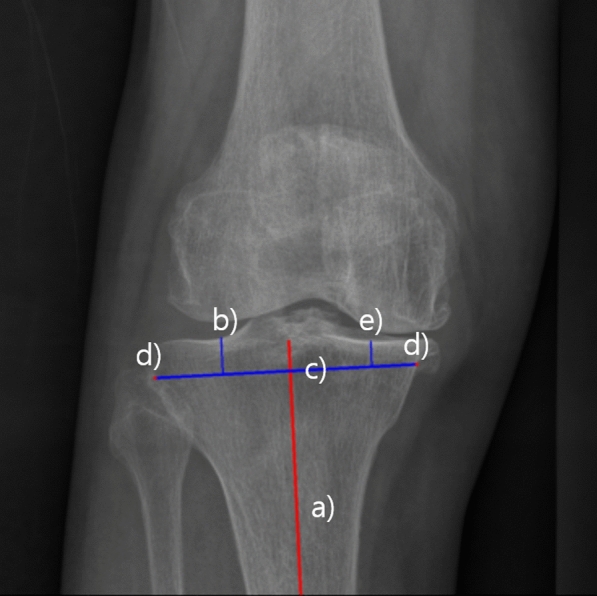

Methods: A total of 13,281 (2938 anteroposterior, 10,343 lateral) knee radiographs obtained from the authors' institute were utilized for model training, with 2302 (1034 anteroposterior, 1268 lateral) images set apart for validation and testing. The templating AI model integrates a pipeline composed of multiple steps for automated implant size estimation. To predict implant size, anterioposterior (AP) and lateral radiograph predictions were merged, selecting the smaller of the predicted sizes to prevent implant overhang. The model's size predictions were validated with 81 real TKA data set apart from the training data, and its accuracy was compared to that of manual templating by an orthopedic specialist. Predictions matching the actual implanted sizes were labeled "exact" and those within one size, "accurate." The influence of patient characteristics on the model's prediction accuracy was also analyzed. The measurement time elapsed for implant sizing was recorded for both the AI model and the orthopedic specialist. Implant position predicted by the model was validated by comparing insert locations with postoperative images.